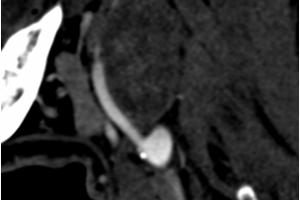

В мае 2019 года хирургами центра сосудистой хирургии им. Т. Топпера была выполнена уникальная операция по удалению гигантского образования шеи, которое давило на сосуды и нервы, угрожая жизни пациента. При исследовании структуры опухоли под микроскопом было установлено, что это шваннома (невринома) – вид доброкачественной опухоли, произрастающей из клеток миелиновой оболочки нерва. Послеоперационный период протекал гладко и на 7 сутки в удовлетворительном состоянии пациент был выписан.